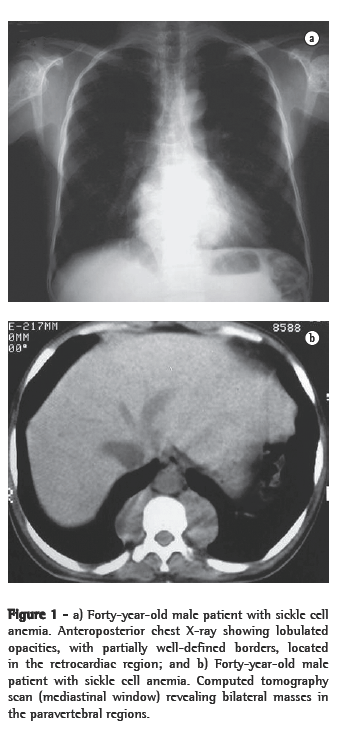

Of the six patients evaluated, four presented lower paravertebral masses. In three cases, the masses were bilateral and relatively symmetric, and, in one, the mass was unilateral (on the right). Regarding the content of the masses, the presence of adipose tissue was confirmed in three patients, and, in one of them, the quantity of adipose material was quite significant. In one patient, the masses were homogeneous, with dense soft parts (Figures 1a, 1b, 2a and 2b).

As associated findings, two patients presented calcifications in the spleen (Figure 4). Both of them had sickle cell anemia. Two of the six patients had undergone splenectomy, and two presented normal spleen imaging findings. Bone alterations related to the underlying disease were identified in three patients.

Radiographically, intrathoracic EMH usually presents as multiple paravertebral masses, with dense soft parts, usually bilateral, lobulated, with well-defined borders, and without accompanying calcifications or bone erosion.(1,4,5,9) This is important for the differential diagnosis of paravertebral neurofibromas, which usually have accompanying bone alterations.(4,10) However, evidence of bone lesions related to the underlying disease is a common finding. On chest X-rays, such masses usually present an aspect of lobulated, double-contour cardiac silhouette in frontal view, as well as an aspect of a lobulated mass projected over the lower vertebral bodies in profile.(13)

On CT scans, masses with dense soft parts, usually homogeneous, with characteristics similar to those described using conventional radiology,(1,2,5,6) and which might or might not be highlighted after administration of contrast material,(4,10) can be seen. This imaging method is important for analyzing the internal structure of the lesions, especially of those that are rich in fat,(5) in order to identify other paracostal masses, and for detecting bone alterations associated with certain hematologic diseases, such as thalassemia and sickle cell anemia.(6) In cases related to thalassemia, sickle cell anemia, or myeloid metaplasia, there can be widening of the medullary cavities of the ribs.(5) All of those aspects were identified in our cases. It is of note that two patients presented calcifications in the spleen, resulting from multiple infarcts, with autosplenectomy. Both of those patients had sickle cell anemia. This finding can also facilitate the differential diagnosis.